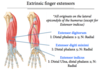

Wrist flexors / extensors? (Flexing is pointing hand down)

Flexors: flexor carpi radialis, flexor carpi ulnaris, palmaris longus

Extensors: extensor carpi radialis longus/brevis, extensor carpi ulnaris

Golfer’s elbow?

Inflammation/tearing of wrist flexor tendons